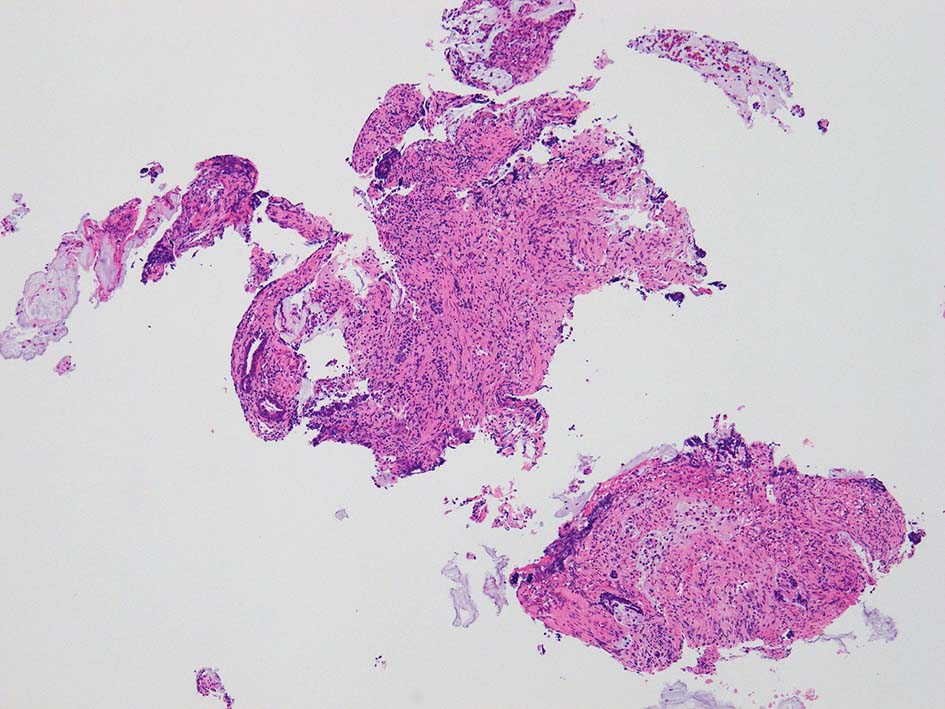

腸管型の腺癌。大腸の高分化腺癌と組織学的に区別は難しい.

desmoplastic fibrosis, 粘液浸潤のみられる組織片にはsig, porのadenocarcinoma浸潤が確認される.

neutrophilic exudate の付着する腸管型腺癌部分. 核はより腫大し円形、vesicularとなっている. 上記腸管型とはCK20, CK7のそまりが異なっていた. 変性のためかもしれない.